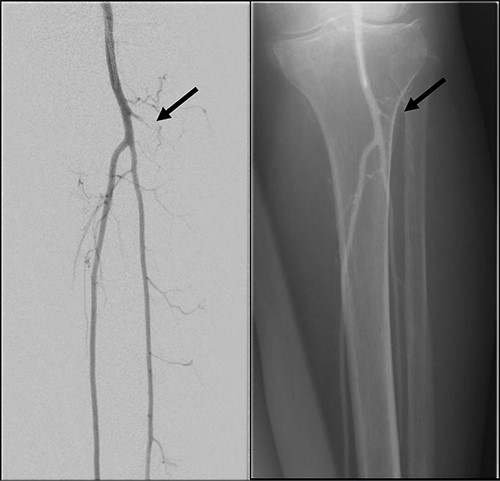

She subsequently underwent left lower limb angioplasty and stenting of the ATA with good results (Figs 4–7) and was started on antiplatelet therapy. Following successful angioplasty, she underwent early wound coverage procedure. A medially based rotation advancement flap was raised for coverage of wound defect. Patient completed 2 weeks course of broad-spectrum antibiotics post-operatively. Patient’s flap was stable and she was allowed partial weight bear over her left lower limb with Darco shoes at post-operative Day 12.

Good arterial flow of the ATA (arrow) after successful angioplasty and stenting.

Arterial flow noted at distal ATA and dorsalis pedis artery (arrow) after successful angioplasty and stenting.